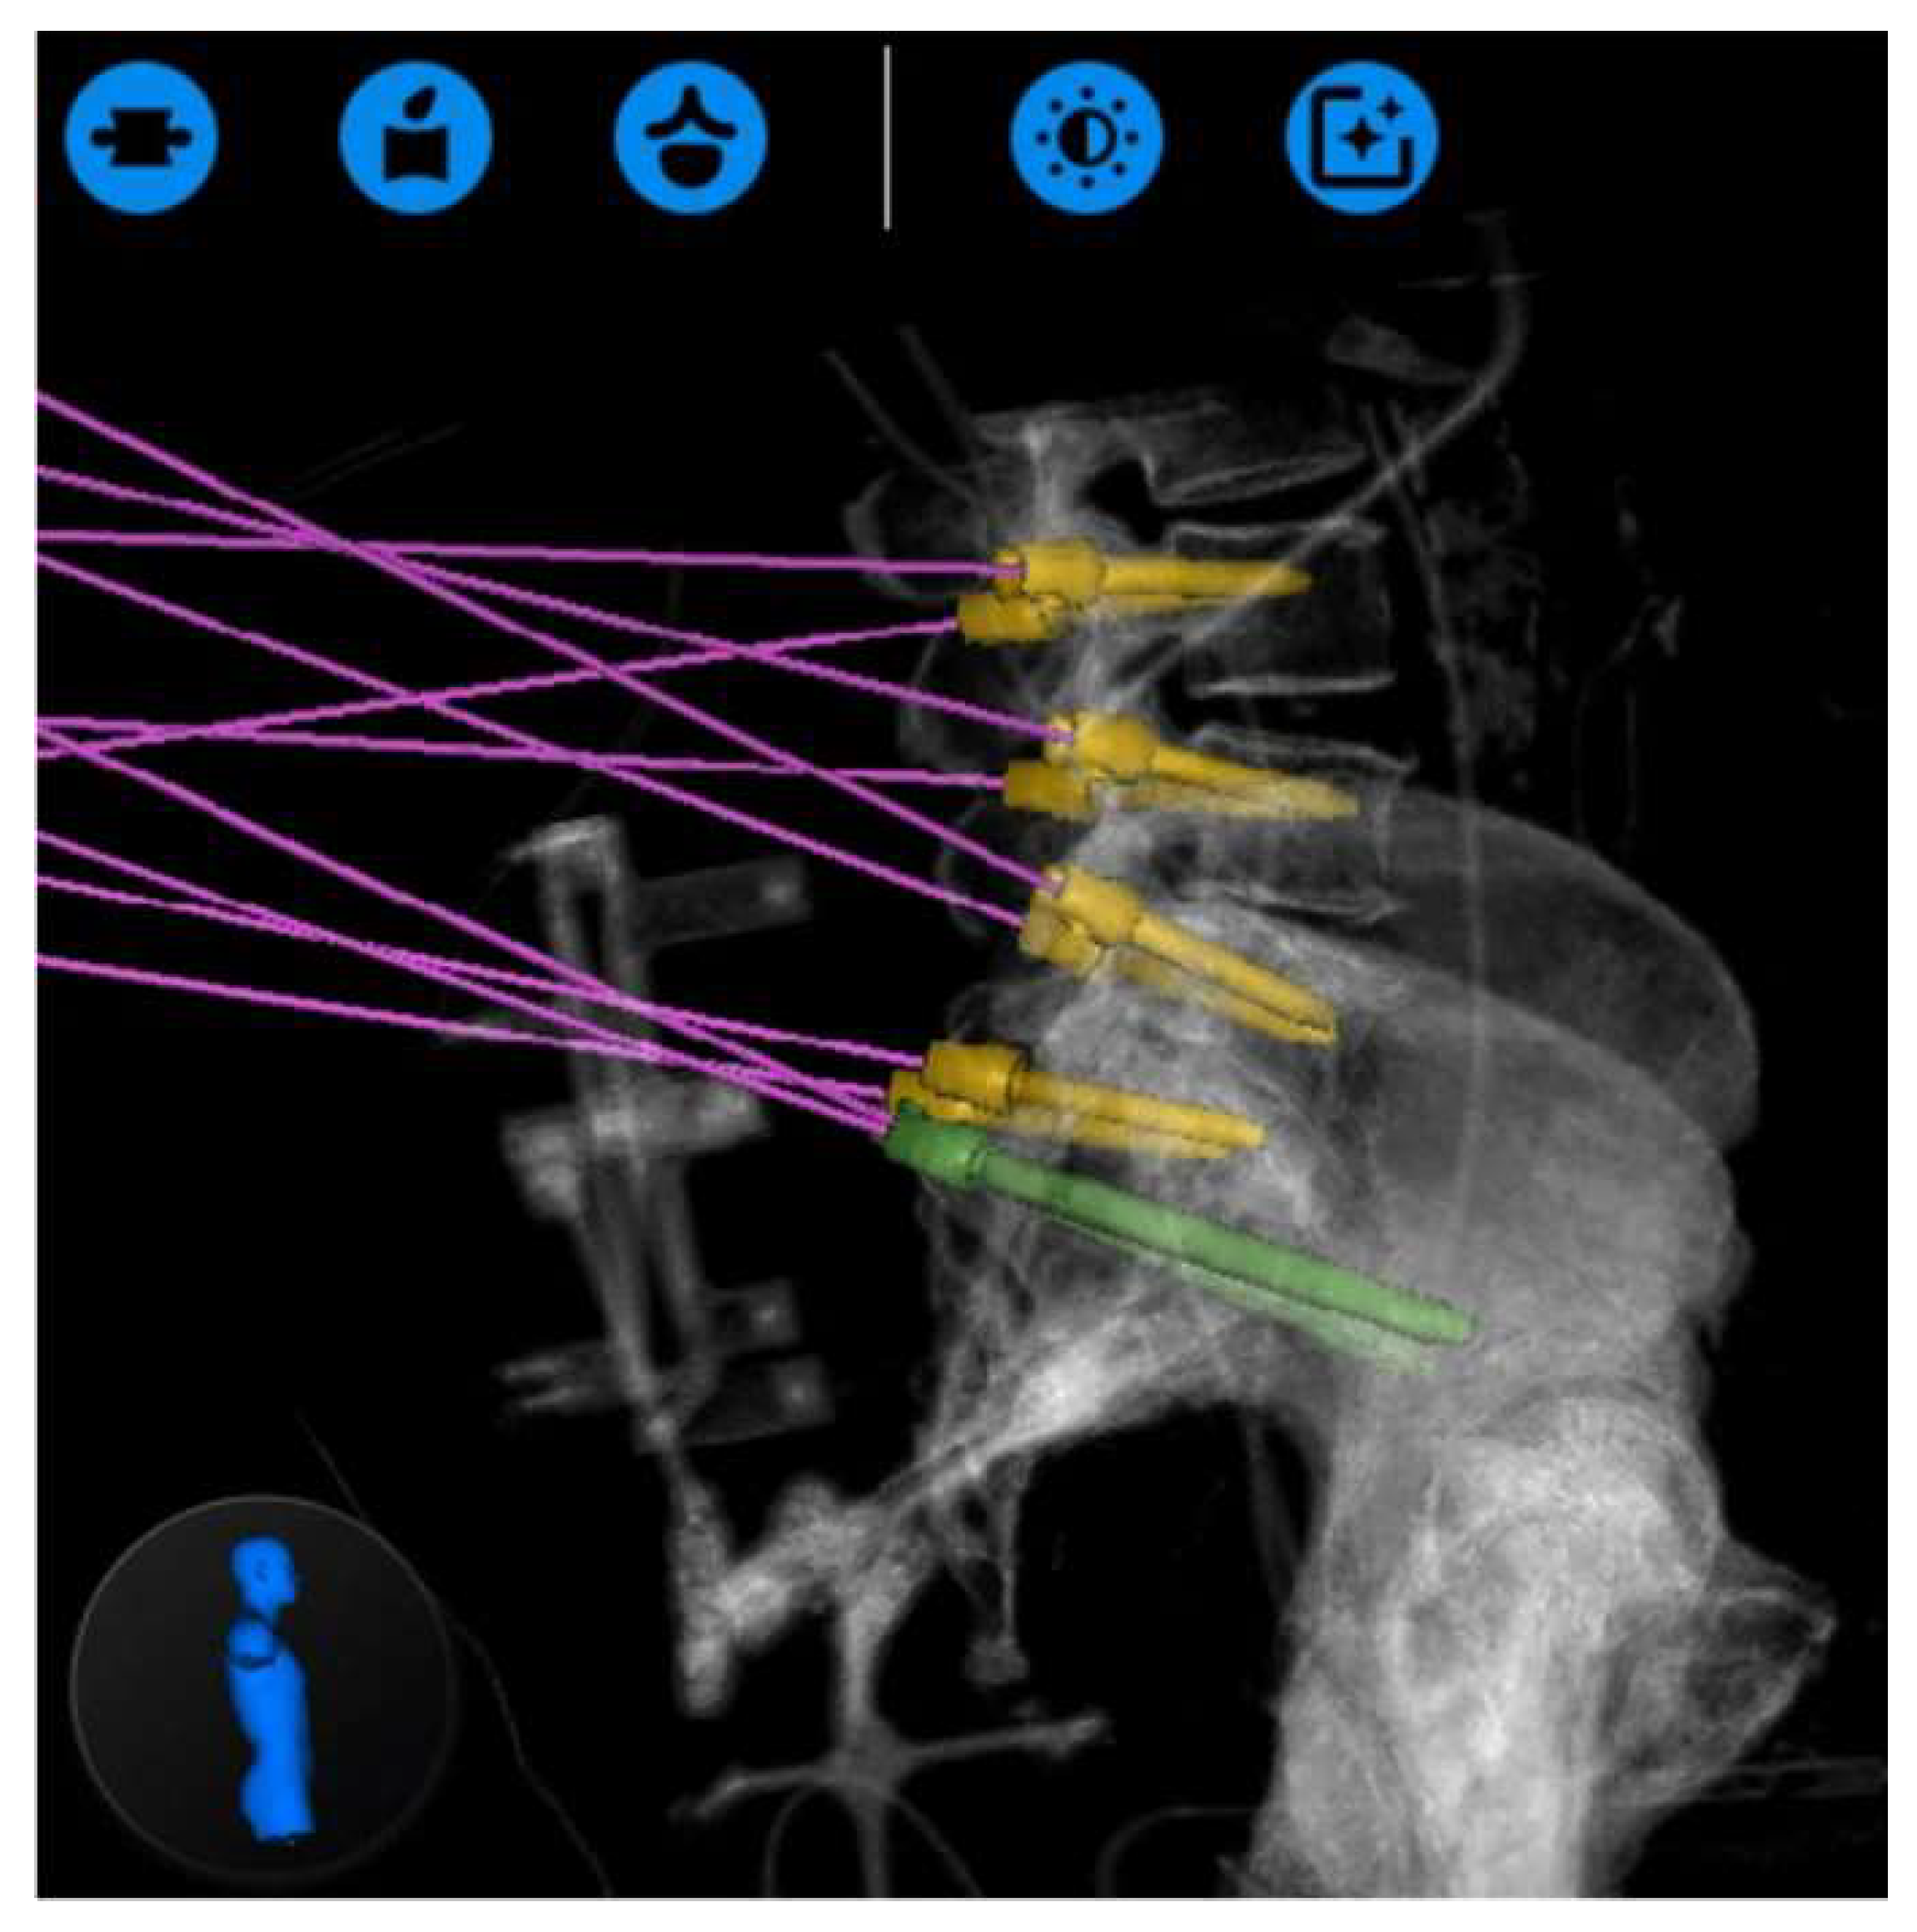

- Dalton, T.; Sykes, D.; Wang, T.Y.; Donnelly, D.; Than, K.D.; Karikari, I.O.; Goodwin, C.R.; Gupta, D.K.; Wiggins, W.F.; Abd-El-Barr, M.M. Robotic-Assisted Trajectory Into Kambin’s Triangle During Percutaneous Transforaminal Lumbar Interbody Fusion-Initial Case Series Investigating Safety and Efficacy. Oper. Neurosurg. 2021, 21, 400–408. [Google Scholar] [CrossRef] [PubMed]

- Lee, N.J.; Khan, A.; Lombardi, J.M.; Boddapati, V.; Park, P.J.; Mathew, J.; Leung, E.; Mullin, J.P.; Pollina, J.; Lehman, R.A. The accuracy of robot-assisted S2 alar-iliac screw placement at two different healthcare centers. J. Spine Surg. 2021, 7, 326–334. [Google Scholar] [CrossRef] [PubMed]

- Laratta, J.L.; Shillingford, J.N.; Lombardi, J.M.; Alrabaa, R.G.; Benkli, B.; Fischer, C.; Lenke, L.G.; Lehman, R.A. Accuracy of S2 Alar-Iliac Screw Placement Under Robotic Guidance. Spine Deform. 2018, 6, 130–136. [Google Scholar] [CrossRef] [PubMed]

- Shillingford, J.N.; Laratta, J.L.; Park, P.J.; Lombardi, J.M.; Tuchman, A.; Saifi, C.; Lehman, R.A., Jr.; Lenke, L.G. Human versus Robot: A Propensity-Matched Analysis of the Accuracy of Free Hand versus Robotic Guidance for Placement of S2 Alar-Iliac (S2AI) Screws. Spine 2018, 43, E1297–E1304. [Google Scholar] [CrossRef] [PubMed]

- Park, C.; Crutcher, C.; Mehta, V.A.; Wang, T.Y.; Than, K.D.; Karikari, I.O.; Goodwin, C.R.; Abd-El-Barr, M.M. Robotic-assisted percutaneous iliac screw fixation for destructive lumbosacral metastatic lesions: An early single-institution experience. Acta Neurochir. 2021, 163, 2983–2990. [Google Scholar] [CrossRef] [PubMed]